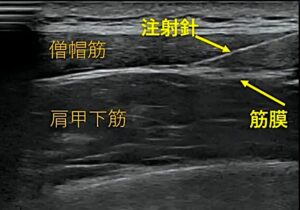

筋膜リリース/ハイドロリリース(先進医療)

肩こりや腰痛の筋肉と筋膜の癒着を剥がす先進医療です。生理食塩水や低濃度の麻酔剤を超音波ガイド下に正確に針を刺入し注入します。当院では先進医療の体外衝撃波と組み合わせダブル先進医療をやっております。

針が筋肉間に見える

薬液が筋膜下に注入